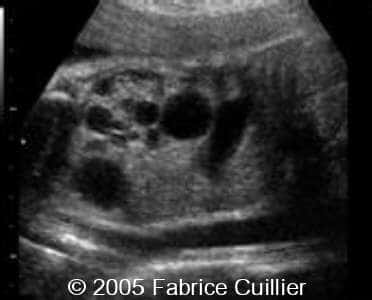

Multicystic kidney disease, unilateral

These are serial scans in a case of unilateral multicystic kidney disease.

Scan at 26 weeks: